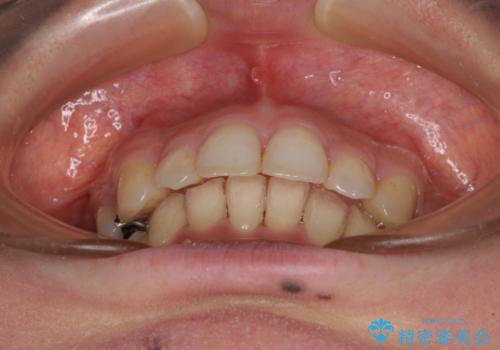

閉じにくい口元 前歯を引っ込める抜歯矯正

- 上下の出っ歯を気にして来院された患者様です。

口元を積極的に引っ込めるために、上下左右の第一小臼歯を4本抜歯することとしました。

元々ディープバイトのため、スペースを閉じている期間に上下前歯が接触してしまい、治療期間が想定よりも伸びてしまいました。